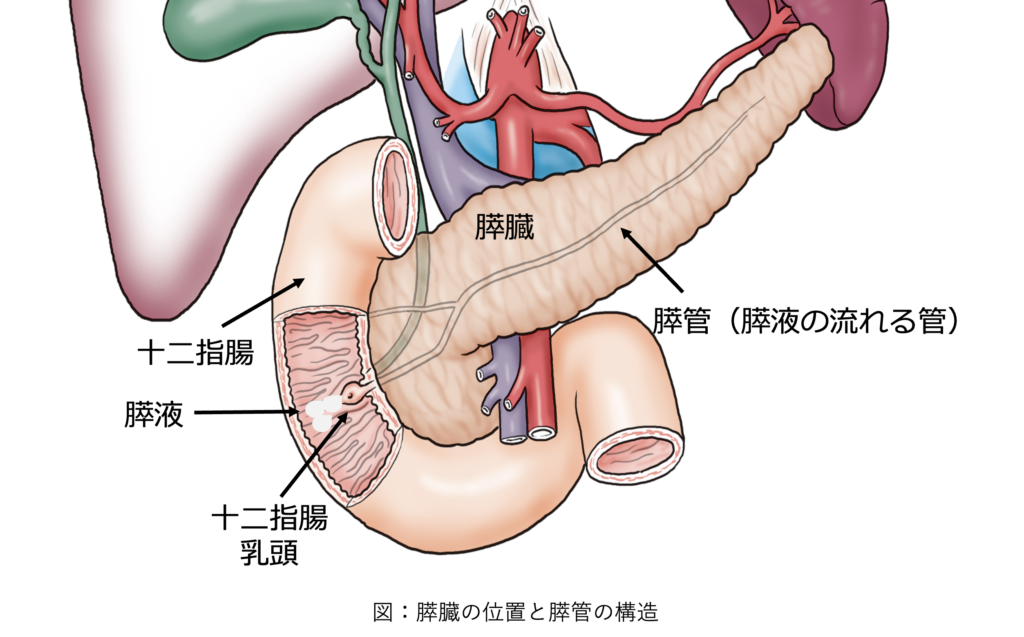

膵管とは、膵臓の中を通る管で、消化液(膵液)を流す役割があります。

通常は細い管(2mm程度)ですが、何らかの原因で太くなることがあります。

これを「膵管拡張」といいます。

一般的には、主膵管径が3mm以上の場合に「膵管拡張」と指摘されることがあります。ただし、膵管の太さは年齢や測定部位、検査方法によっても見え方が変わります。

大切なのは、数値だけで判断することではなく、

膵管がどの部分で拡張しているのか、途中で急に細くなっていないか、

膵嚢胞や腫瘤を伴っていないかを総合的に確認することです。

膵管拡張は、膵管の一部が狭くなったり、膵液の流れが悪くなったりすることで起こります。 原因としては、膵がん、IPMN(膵管内乳頭粘液性腫瘍)、慢性膵炎などが代表的です。

① 膵がん

膵がんによって膵管の一部が狭くなると、その上流側に膵液がたまり、膵管が拡張することがあります。

特に、膵管が途中で急に細くなっている場合や、膵管拡張の先に小さな腫瘤が疑われる場合には、 膵がんの可能性も考えて詳しく調べる必要があります。